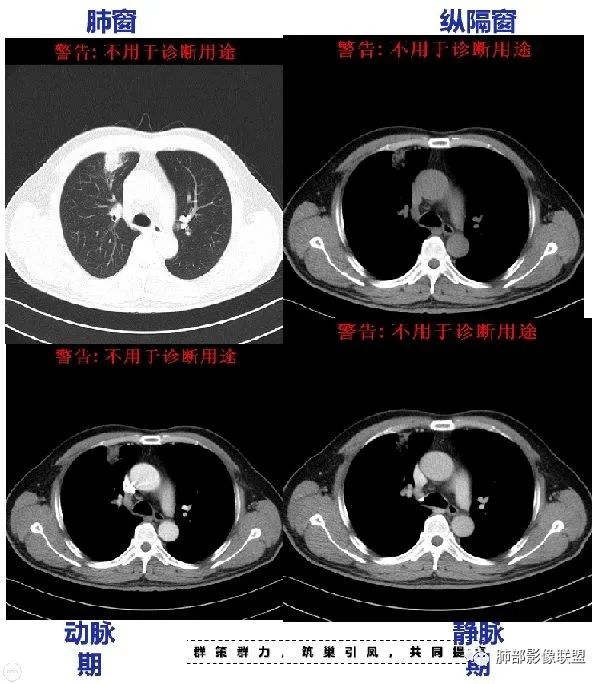

最后结果:

这个是炎症,治疗一月后复查图片。

病例小结

回顾性分析本病例,小编觉得鉴别诊断聚焦于肺鳞癌和炎性病灶(包括结核)之间,这个病灶的炎性征象大于恶性征象;以下是这个病例的的炎性征象:①病灶边缘平直收缩为主,也缺少典型的分叶毛刺;②支气管走行于病灶中央截断,断端比较圆钝;③近端引流支气管壁增厚;④整体强化不显著,坏死区太圆太规整,边缘隐约显示强化的环;⑤血管走形自然,未见明显破坏征象;⑥胸膜外脂肪间隙增宽,胸膜广基地增厚,未见栽赃;⑥52岁偏年轻(此条也不大支持鳞癌)

虽然本例患者支气管截断,病灶中央截断炎性及恶性都可以,断端向病灶一侧圆钝更支持炎性。 医学百科网 | YxBaike.Com